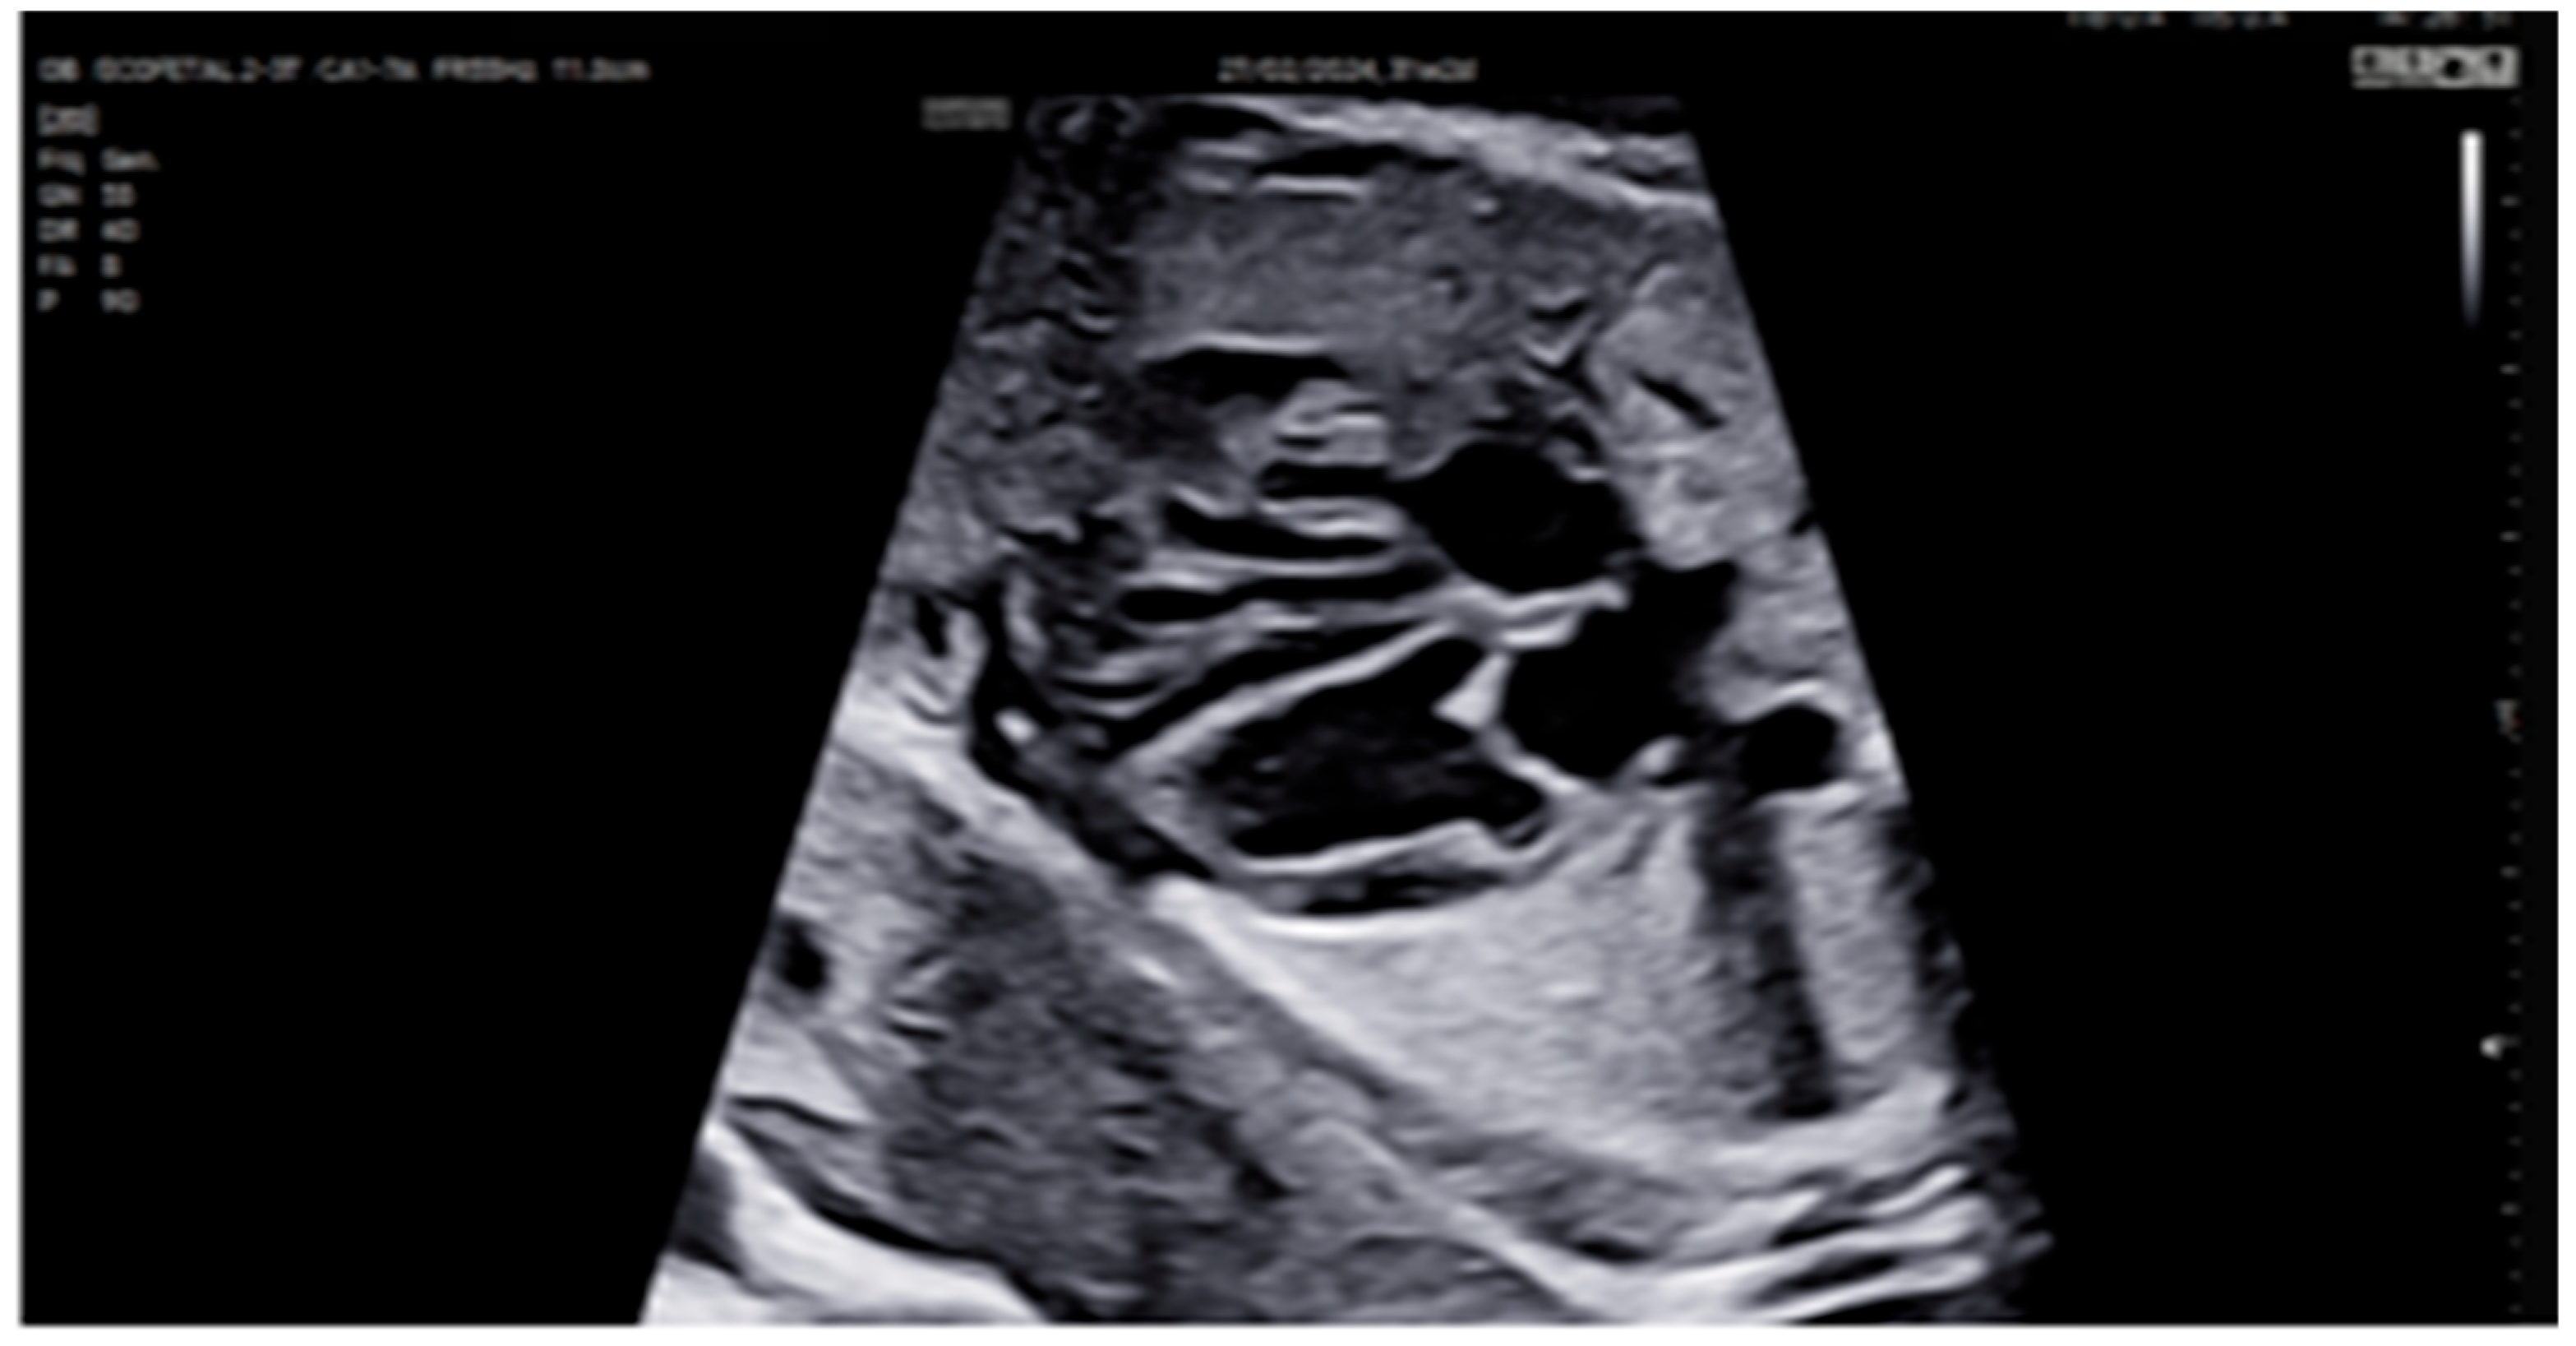

| 26 + 0 | Start of dexamethasone 4 mg/day | 60 | SF increased from 34% to 47%, but qualitative contractility decreased | Mild edema; no beta- agonists used |

| 28 + 0 | First IVIG cycle (65 g total) | 75 | SF increased to 52%; mild improvement in contractility | Initiated due to signs of fibroelastosis |

| 31 + 2 | Post-IVIG peak response | 70 | SF: 59% (LV), 52% (RV); marked biventricular improvement | Aortic isthmus 3 mm (Z-score –1.65) |